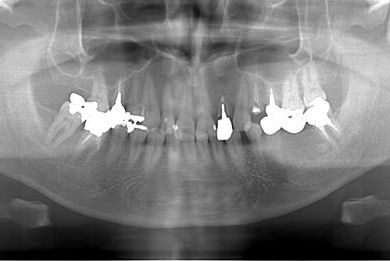

抜歯即日スピードインプラント治療

| 主訴 | 前歯が折れていてないので、インプラント治療を希望。 | ||||||||||||||||||||||||||||||||

| 治療内容 | インプラント1本(抜歯即日スピードインプラント)、ハイブリッドセラミッククラウン1本 | ||||||||||||||||||||||||||||||||